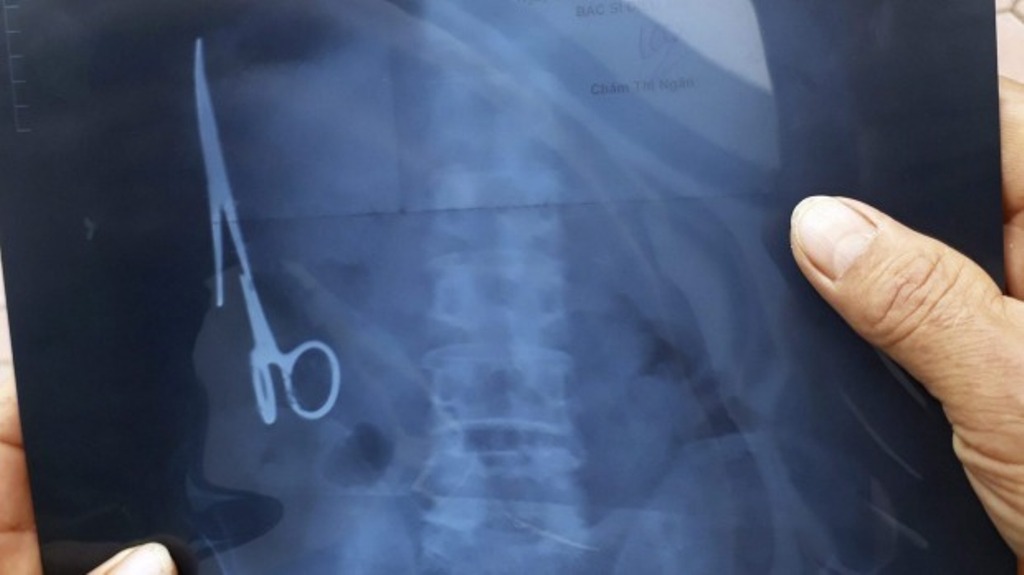

An X-ray of Ma Van Nhat's stomach show where the scissors have been hiding for years.

The 15 cm (six inch) long instrument had broken apart and become lodged in Nhat's stomach. They were removed in an operation.